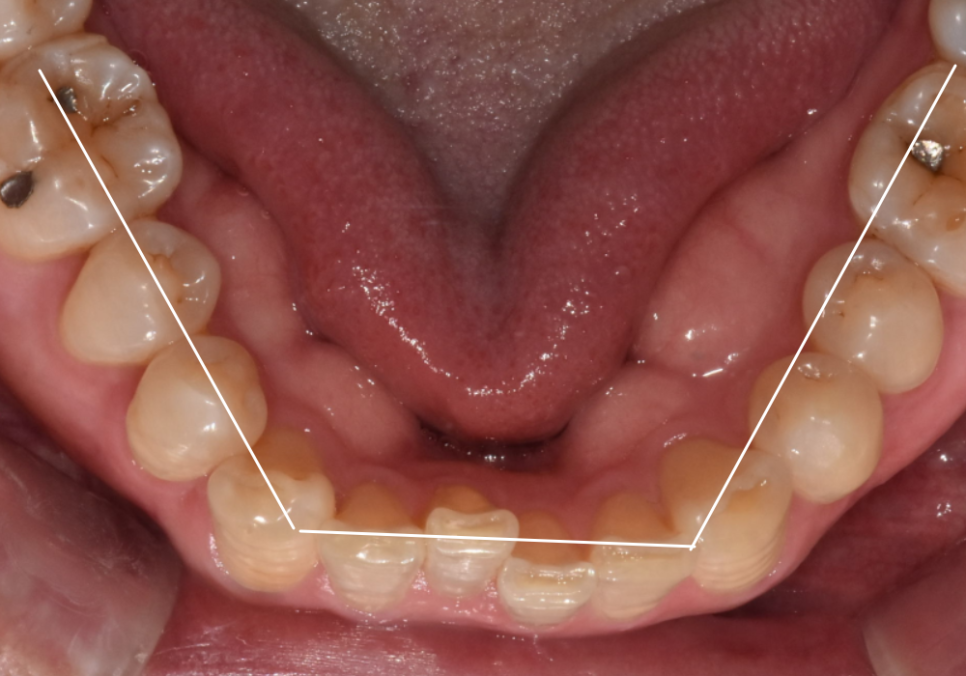

치아 라인을 위에서 내려다보니

매끄러운 U자 아치형이

앞니로 인해

'ㄷ' 자로 꺾인 모습이었습니다.

230613

이런 경우 굳이 전체 교정이라는

큰 공사를 벌릴 필요가 없습니다.

안으로 들어간 치아만

밖으로 살짝 꺼내주면

치아 배열이 마법처럼

가지런해질 수 있기 때문이죠.